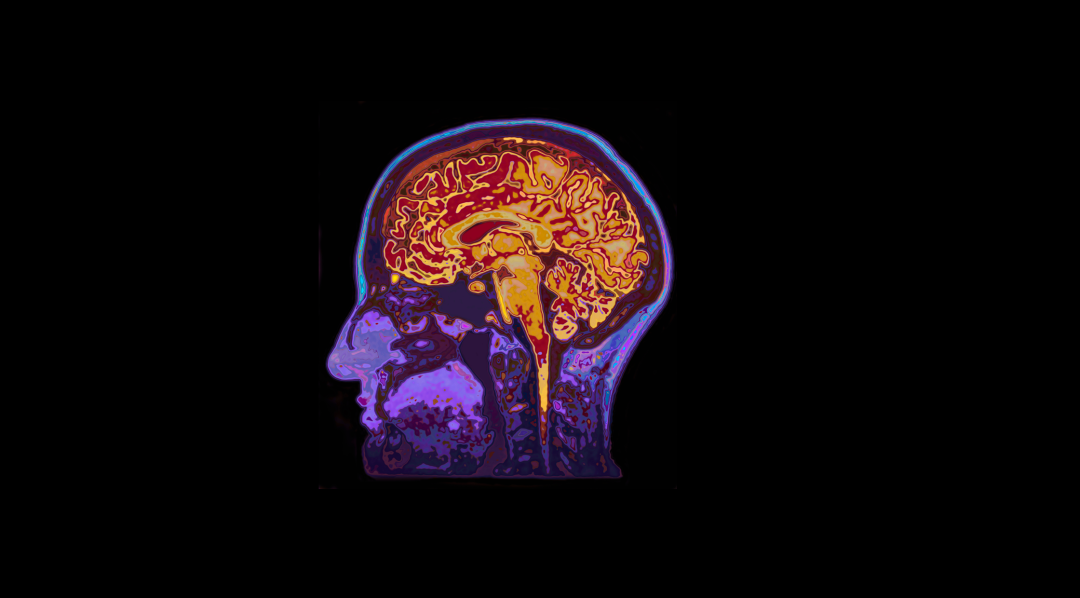

然而,高质量睡眠的脑电波节律有助于脑脊液(CSF)进入大脑,并“清洗”有害代谢物[1]。因此,缺觉不仅导致“秃头”,还会伤害大脑,睡眠时间不足和睡眠质量差,都已被证明能够增加认知障碍风险及阿尔茨海默病(AD)病理负担[2]。

近日,来自华盛顿大学的Brendan P. Lucey团队,在Alzheimer’s & Dementia发表了一项临床交叉试验结果[3],让我们对睡觉其实是“清洗”大脑有了更清晰的认知。

总体而言,本研究表明一夜睡眠不足能够通过破坏大脑清除机制,减少中枢神经系统中Aβ、tau和p-tau的清除,导致CSF中Aβ、tau和p-tau的浓度在一夜之间升高,而在血浆中降低。